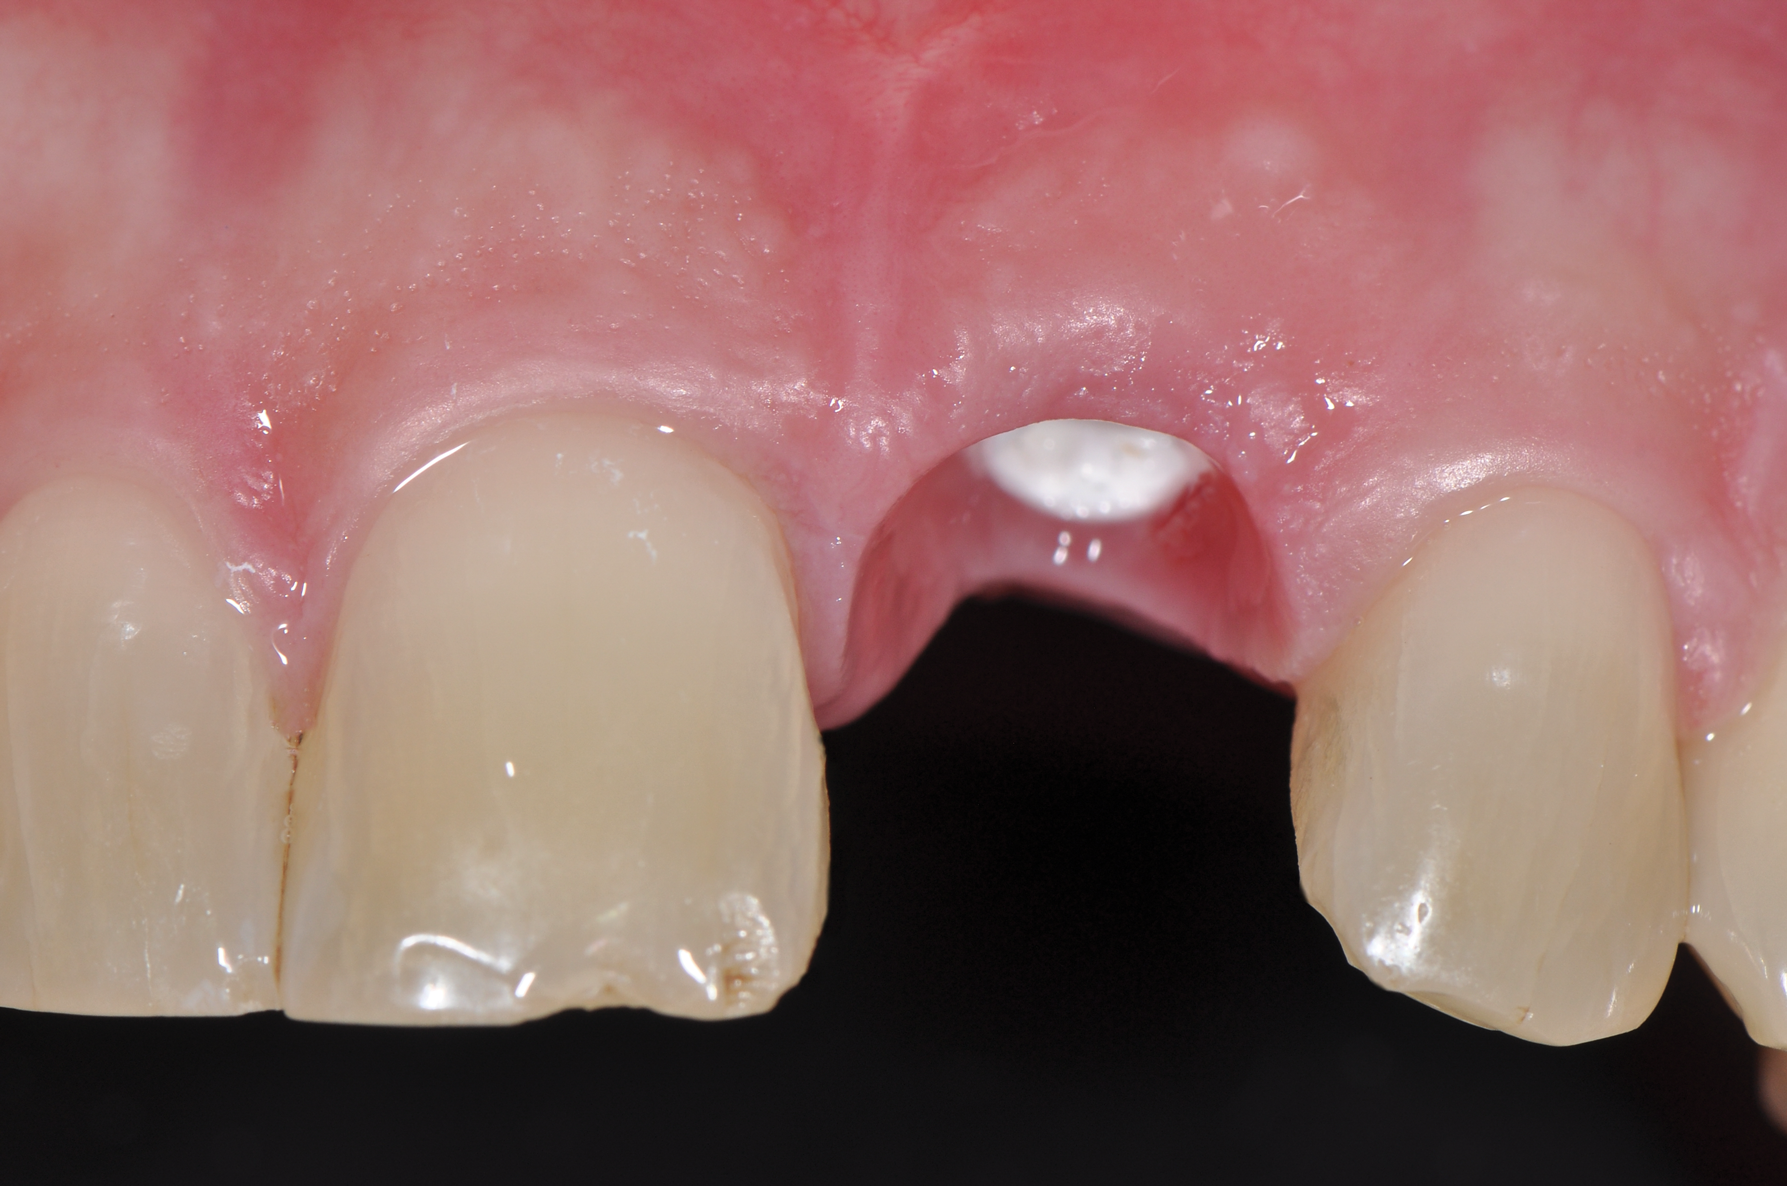

Fig 9. Healed implant site 12 weeks after surgery before re-entry.

Figure 9

Fig 3. Soft tissue with zirconia implant free of inflammation.

Figure 3

While more scientific evidence showing a lower tendency toward peri-implantitis may still need to be provided for ceramic implants, the essential argument for these implants based on clinical experience is the excellent and almost consistently inflammation-free peri-implant soft-tissue condition (Figure 3).